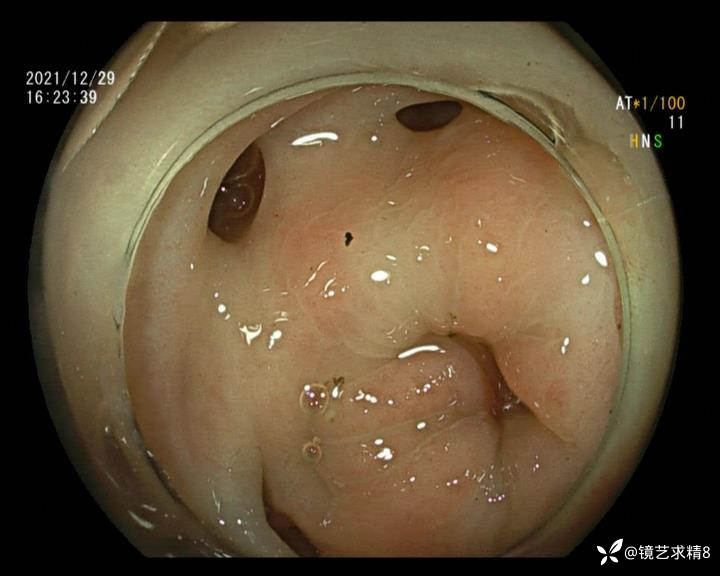

患者以消化道出血入院,胃镜未见异常,肠镜进入乙状结肠就看到很多憩室,同时还看到肠腔用清肠药后移动下来1枚尖锐的枣核,这么多憩室,这个枣核扎入憩室的机会非常大,推测应该是掉入一坑🕳就算出来还会有很多坑🕳🕳🕳等着,掉入憩室内很容易刺破血管,这可能就是消化道出血的原因,继续前进可以看到有一些憩室内翻,还有一些息肉,问题来了,那么多憩室,犯罪分子是抓住了,它在那些憩室内作过案?到达回盲部后挨个冲洗,但憩室大小又不足以把镜头进入憩室内观察,针对有血块的憩室冲洗后可疑出血的以夹子闭合或套扎,取出枣核,如果有锥形透明帽可能钻入憩室精准电凝效果更好,若内镜下操作失败介入治疗成功率更高,经内镜下治疗后观察未再出血出院。